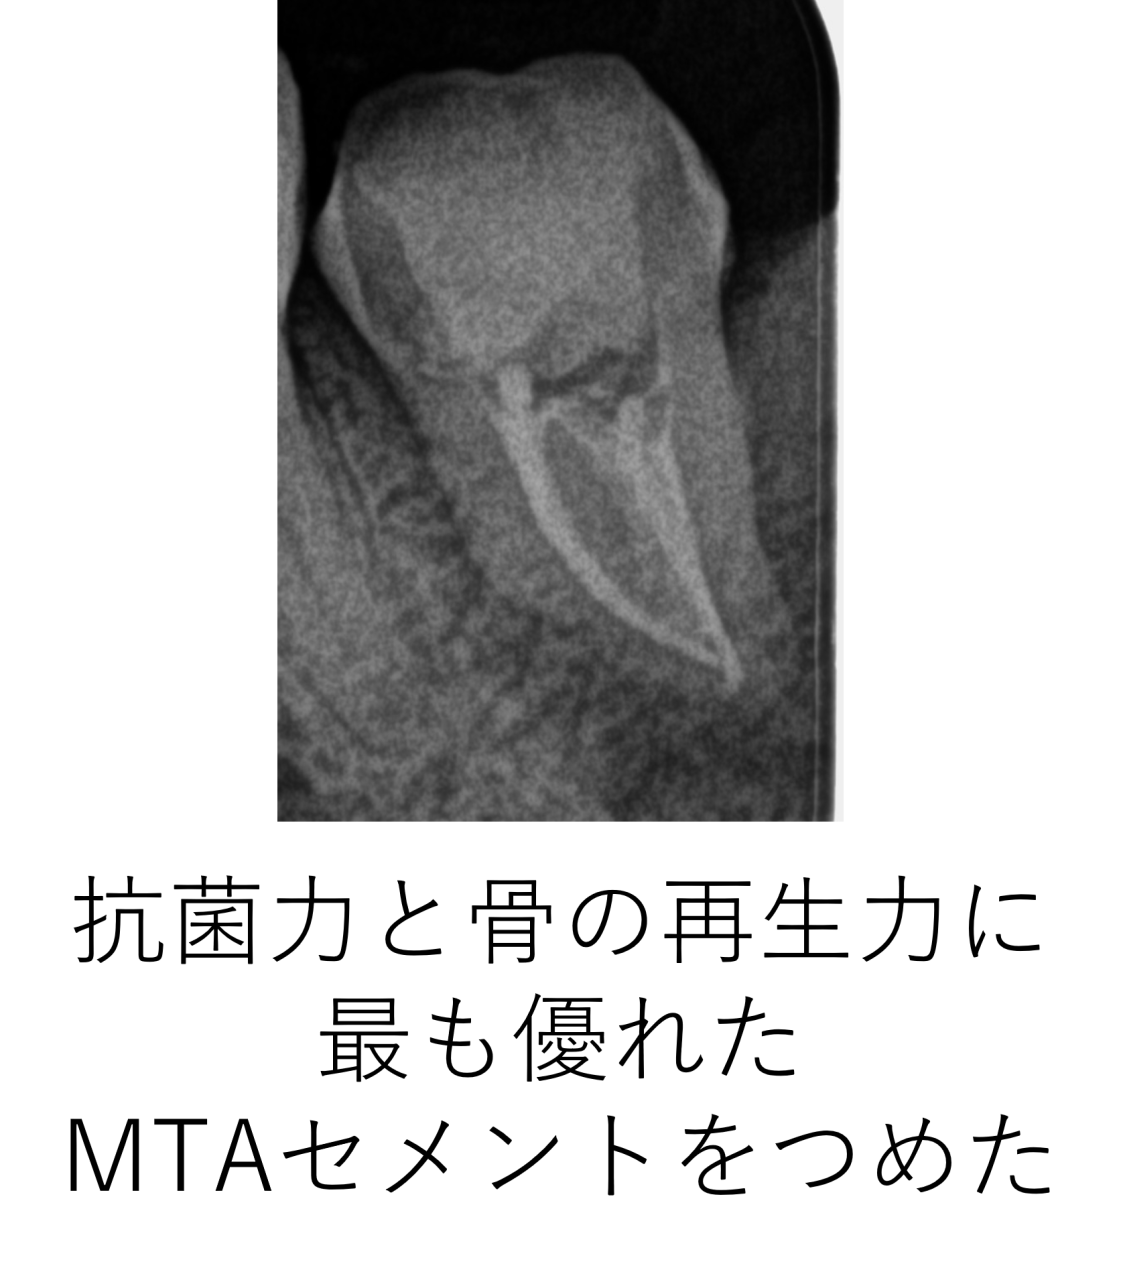

次回の来院時、患者様は痛みもなく違和感も無くなったとのことで、歯の状態も良かったため最終的な抗菌剤(薬)をつめて完了しました。抗菌剤は現在最も長期に渡り抗菌作用が続き、骨を再生する能力が高いMTAセメントを使用しました。